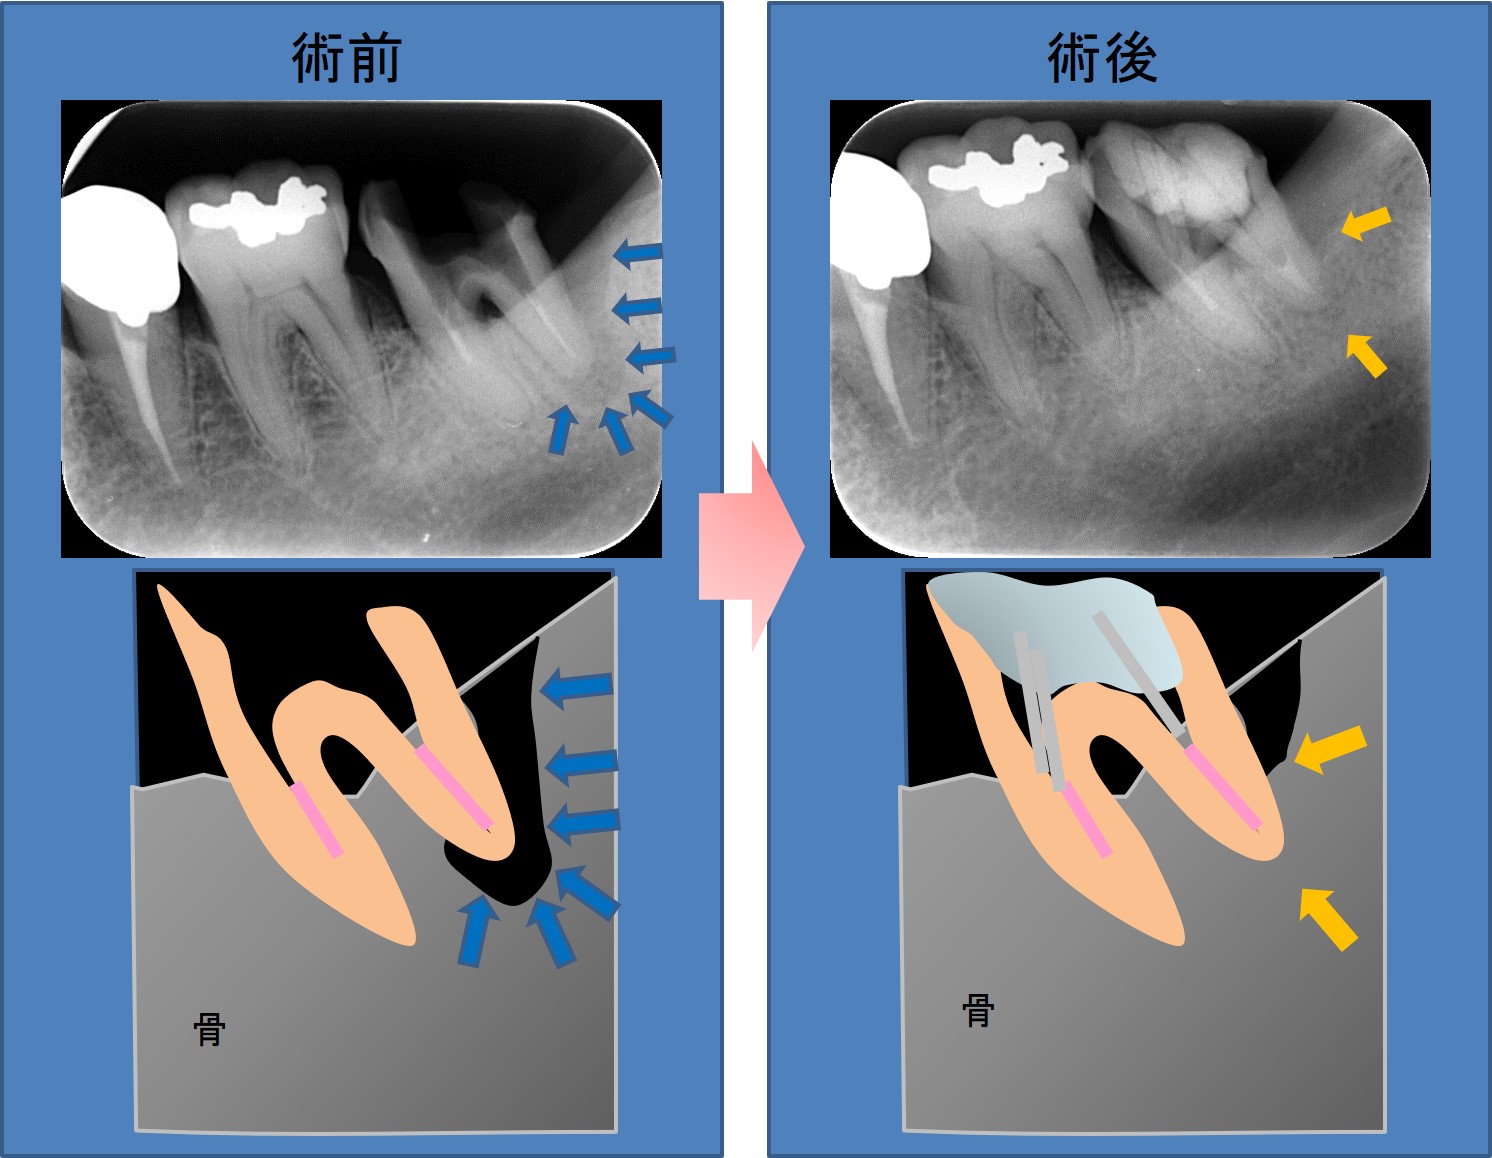

← 205.歯周病の骨再生